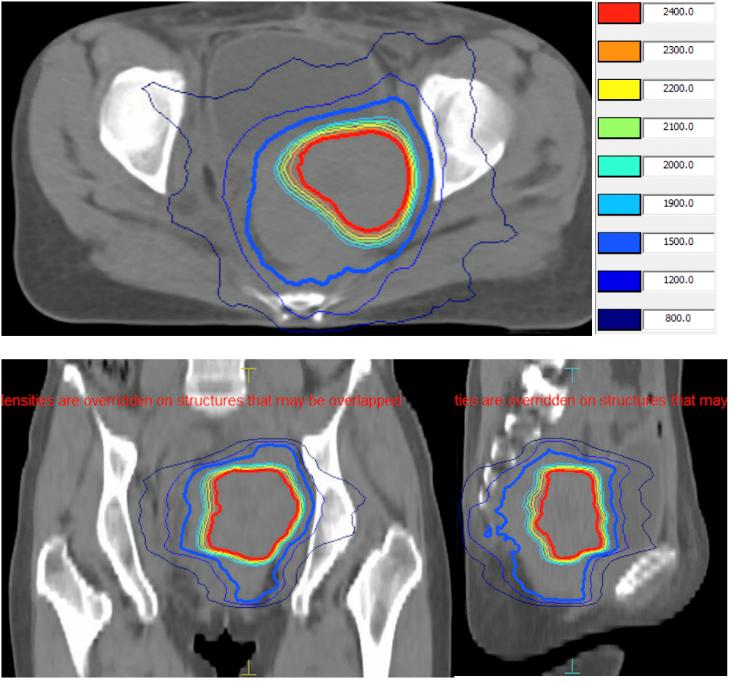

第一周期:2022-8-24开始盆腔病灶放疗d1-3,PTV(含所有病灶):5Gy×3f,PGTV(避开直肠):8Gy×3f, PD-1抗体(替雷利珠单抗)免疫治疗d2,FOLactis瘤内注射治疗两次d3、d7。

第二周期:2022-9-15盆腔病灶放疗d1,PTV:5Gy×1f,PGTV:8Gy×1f。PD-1抗体(替雷利珠单抗)免疫治疗d2,FOLactis第3次瘤内注射治疗d2。

图1. 放疗靶区图